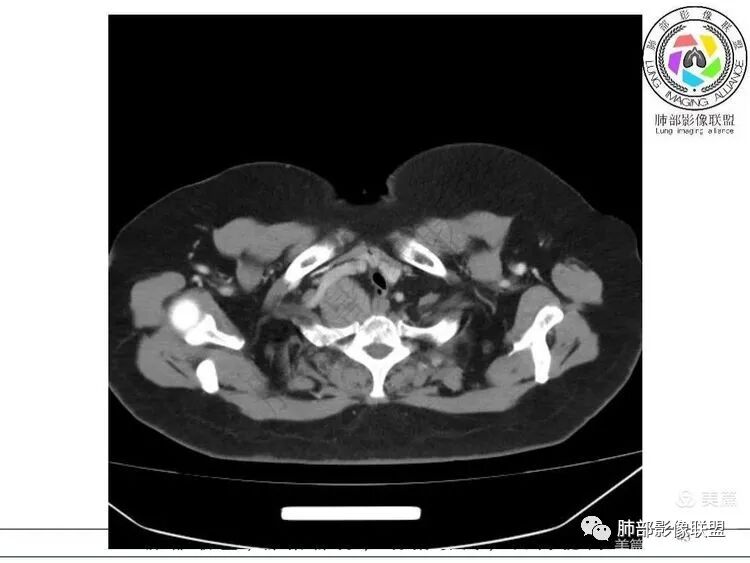

推压血管,进入颈部

南边:支持:神经源性,从病灶的形态突入颈部,跨多区域

1. 右上胸廓入口区类椭圆形块影,边界清楚光整,纵向“嵌顿”于颈根部及上纵隔,向上推移右锁骨下动静脉,向外下方推移上肺胸膜及肺组织(肺血管、支气管),向前推移上腔静脉,界限清楚。

神经鞘瘤是周围神经最常见的肿瘤,起源于神经鞘膜的施万细胞,生长缓慢,包膜完整,与起源神经紧密相连,绝大多数为良性,恶性罕见;纵隔内神经源性肿瘤90%发生于后纵隔,发生在交感神经链或肋间神经的椎旁;偶尔,神经鞘瘤可位于中纵隔或前纵隔,最常见的发生于迷走神经,其次是喉返神经、膈神经等。所以神经源性肿瘤很重要一点在于解剖,一般只要存在神经组织,都可以发生神经源性肿瘤;后纵隔神经鞘瘤最常见的位置是脊神经刚出椎间孔的位置,并沿着肋间神经分布,所以一般横径大,上下径小,而且来源于神经根的可呈哑铃状跨越椎管内外生长;而来源于前或中纵隔神经的迷走神经或喉返神经等是上下走形,所以神经鞘瘤常表现为上下径长;神经鞘瘤在病理上包括A区和B区,Antoni A区富含细胞,密度较高,Antoni B区含有较多粘液成分,密度较低,可见囊变、出血,如果出血,血肿可见机化、钙化。